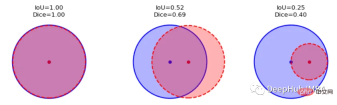

我们如何度量模型的性能?一个成功的预测是一个最大限度地扩大预测和真实之间的重叠。

这一目标的两个相关但不同的指标是Dice和Intersection / Union (IoU)系数,后者也被称为Jaccard系数。两个指标都在0(无重叠)和1(完全重叠)之间。

这两种指标都可以用于类似的情况,但是区别在于Dice Score倾向于平均表现,而IoU则帮助你理解最坏情况下的表现。

我们可以逐个类地检查度量标准,或者取所有类的平均值。这里将使用monai.metrics.DiceMetric来计算分数。一个更通用的方法是使用torchmetrics,但是因为这里使用了monai框架,所以就直接使用它内置的函数了。